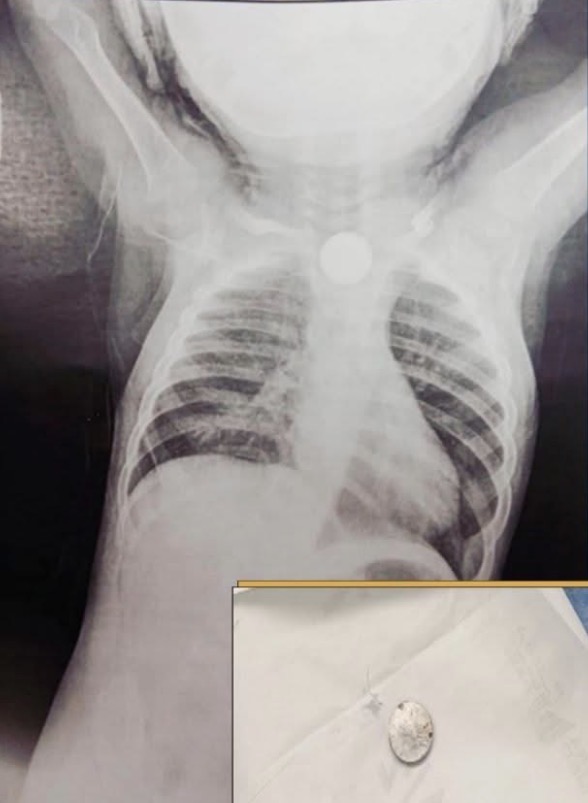

أوضح الأطباء بالمجمع أنه بعد مناظرة الحالة وإجراء أشعة على الصدر، تبيّن وجود جسم غريب يُعيق مجرى الطعام والتنفس، وعلى الفور تم إدخال الطفل إلى رعاية الأطفال لاستكمال الفحوصات والعلاج اللازم، ثم نقله إلى غرفة العمليات لإجراء تدخل عاجل بالمنظار.

تمكن الفريق الطبي خلال العملية التي أُجريت تحت مخدر كلي، من استخراج الجسم الغريب الذي تبيّن أنه حجر بطارية لعبة أطفال صغيرة، في إجراء دقيق استغرق دقائق معدودة أنقذ حياة الطفل من مضاعفات خطيرة محتملة.